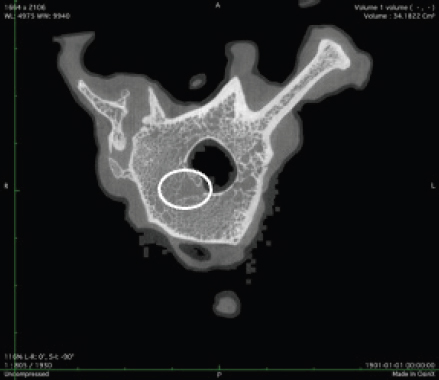

μCT scan

Using X-ray imaging, every volumetric element of the sample, not just its surface contour, was digitized. We obtained almost 24 GB of data, which required specialized software for its analysis. The trabeculae in the vertebral body can be seen clearly in Figure 7. After analyzing the different sections, we discovered that there are locations in the vertebral body where porosity is very high, and it is reasonable to assume that these cavities are filled with connective tissue. The bone tissue in these locations is more fragile; there has been a change in the bone structure, and there would be an increased fracture risk.

Fig. 7. Visible defects in the canine L2 vertebra.

It is possible that a single examination, such as histomorphometry, will not be sufficient; in that case, more advanced techniques, such as μCT, could be additionally used. Using this technique, we detected holes in the vertebral body that were caused by osteoporosis.

We anticipate that, with decreased BV/TV and a decrease in the size of the trabeculae, the trabeculae would be able to sustain less external force. μCT reveals the pores that cause the vertebral column to be more fragile and susceptible to breaking.